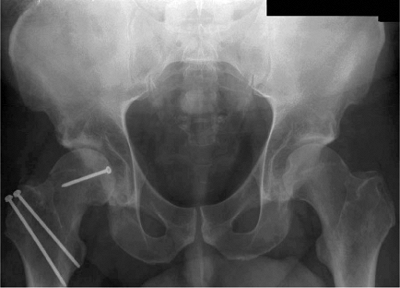

images are used to confirm fracture reduction, hardware placement, and

concentric hip reduction (Fig. 44.9).

![]() |

Figure 44.14. Postoperative AP radiograph.

demonstrates excellent reduction of the femoral-head fracture and a

congruent hip joint (Fig. 44.14). At the

3-month follow-up, the fracture was healed, and the patient was full

weight bearing on the affected leg. At the 6-month follow-up, the

patient remained pain free with excellent range of motion in his hip.

No radiographic evidence of avascular necrosis was found at latest

follow-up.